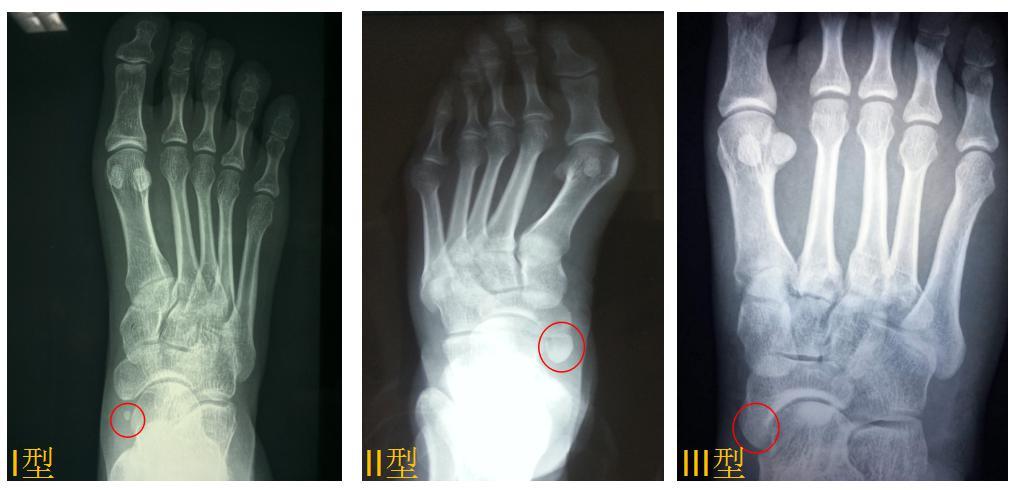

副舟骨形态各异,大小不一,位于舟骨的内后侧,既可以和胫骨形成骨性